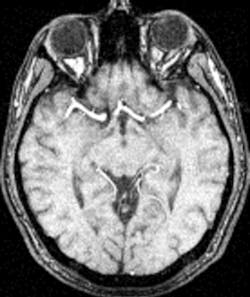

In short it appears that 3T MRI Systems are not just stronger but also more efficient and more equipped to adapt to the future demands of MRI exams. A name brand MRI vendor told me 3T scanners can perform routine MRI scans and add value by creating and handling additional volume with newer offerings such as breast MRI, MR angiography and cardiac scanning which makes them more valuable than a 1.5T system.